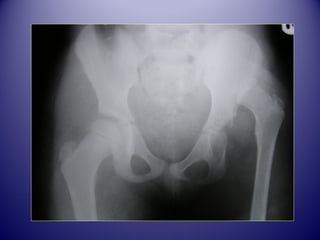

LLAA LLUUXXAATTIIOONN

CCOONNGGEENNIITTAALLEE DDEE HHAANNCCHHEE

RAPPEL

ANATOMIQUE

Ilion

Cotyle

Pubis

Tête fémorale

Ischion

Diaphyse

AASSPPEECCTT SSEEMMIIOOLLOOGGIIQQUUEE

DDEE LLAA LLCCHH

Confirmation dduu ddiiaaggnnoossttiicc cclliinniiqquuee

Avant 4 mois

Après 4 mois

radiographie

BBIILLAANN DDEE LL’’EEXXAAMMEENN

CCLLIINNIIQQUUEE

 HHaanncchhee iinnssttaabbllee

 HHaanncchhee lluuxxaabbllee BBAARRLLOOWW++

 HHaanncchhee lluuxxééee rréédduuccttiibbllee OORRTTOOLLAANNII++

 HHaanncchhee lluuxxééee iirrrréédduuccttiibbllee BBAARRLLOOWW--

OORRTTOOLLAANNII--

 BBaassssiinn AAssyymmééttrriiqquuee CCoonnggéénniittaall

DDEEPPIISSTTAAGGEE DDEE LLAA LLCCHH

CCoonncclluussiioonn

 AAffiinn dd’’éévviitteerr cceettttee eessccaallaaddee

tthhéérraappeeuuttiiqquuee,,llee ddééppiissttaaggee eenn

mmaatteerrnniittéé eett lloorrss ddeess pprreemmiièèrreess

sseemmaaiinneess eesstt pprriimmoorrddiiaall!!!!

 EEnnttrree 8800 eett 9900%% ddeess hhaanncchheess

ddééppiissttééeess << 33mmooiiss oonntt uunn bboonn

pprroonnoossttiicc..